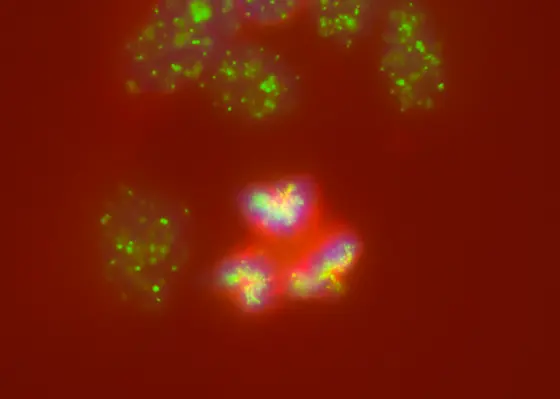

In neuroblastomas, cell division gets out of hand: instead of dividing chromosomes (blue) evenly among daughter cells, several spindle poles (green) and spindle apparatuses (red) form, even leading to the breakage of chromosomes or their incorrect division.